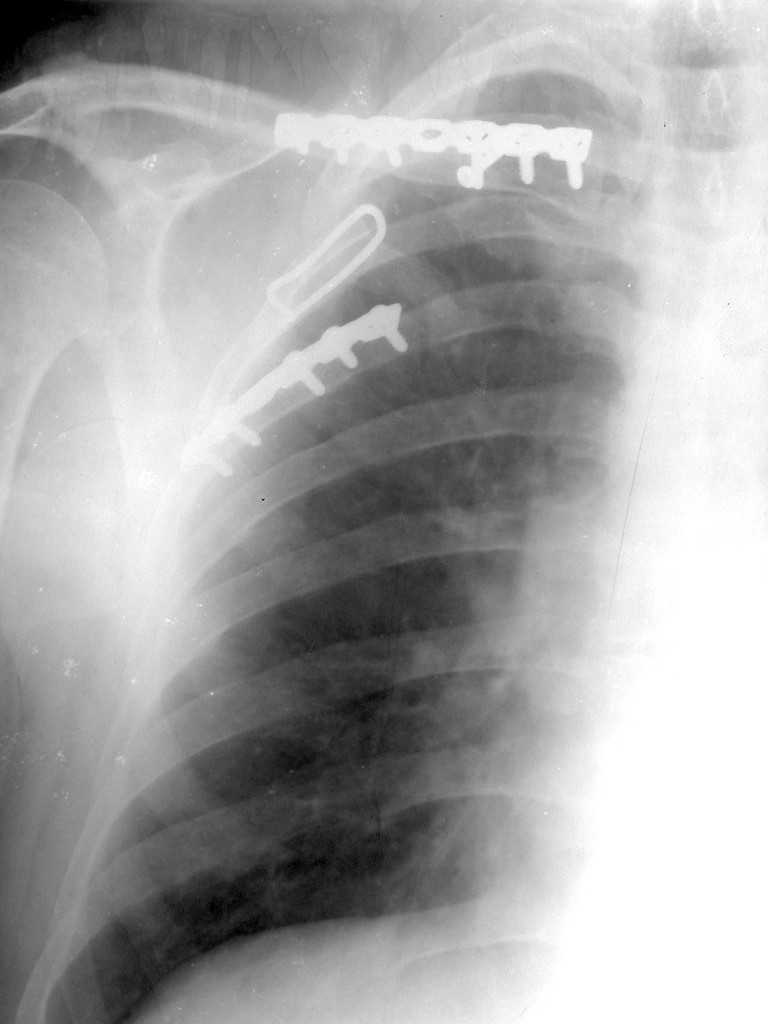

Re: Перелом лопатки, ключицы, ребер

Мы в таких случаях оперируем в 2-а этапа:

1. Стабилизация грудной клетки(фиксируем ребра по одной из линий рекон. LCP)

2. Остеосинтез лопатки из заднего доступа(рекон.LCP, LC-LCP 3,5мм, Т-обр.LCP 3,5мм); ключицу стандартно

К сожелению доктор который занимается грудной клеткой в отпуске, у себя нашёл только вот этот снимок

С Уважением А.Миронов